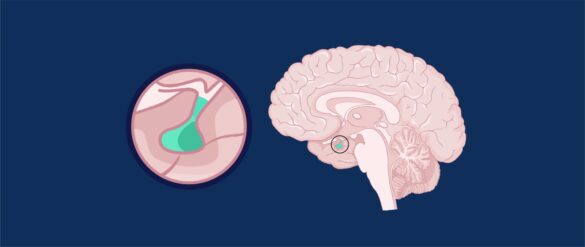

La hipófisis y su rol en el desarrollo

La hipófisis, o glándula pituitaria, es un órgano clave en la regulación hormonal del cuerpo humano. Asimismo, se trata de un órgano que incide en el desarrollo de los seres humanos, tanto a nivel cerebral como físico. Pero, ¿cómo influyen las hormonas liberadas por la…